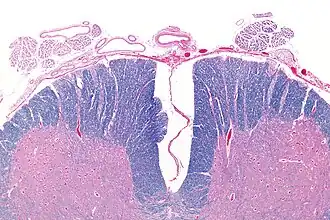

Micrograph showing an axial section of the anterior spinal cord and anterior spinal artery (top-middle of image). LFB-HE stain.